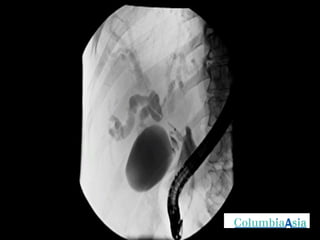

ERCP (Endoscopic Retrograde Cholangio Pancreatography) is an endoscopic procedure used to diagnose and treat issues in the bile and pancreatic ducts. It involves positioning an endoscope and using x-rays to view the ducts while performing procedures like draining bile ducts, removing gallstones, and placing stents. Potential complications include pancreatitis, bleeding, infection, or perforation. Careful pre- and post-procedure steps like monitoring and antibiotics are important to minimize risks.